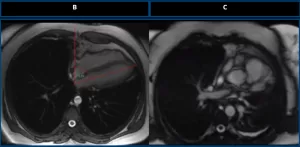

Axial chest MRI of a healthy control (A) demonstrates normal cardiac rotation. A vertical reference line is drawn along the spine. The cardiac axis forms an angle of less than 60° indicating normal positioning.

Axial T1-weighted MRI (B) shows excessive clockwise rotation of the heart, with a cardiac axis angle greater than 60°, a characteristic finding of left pericardial agenesis. Axial T2-weighted MRI (C) confirms the abnormal cardiac orientation, supporting the diagnosis.